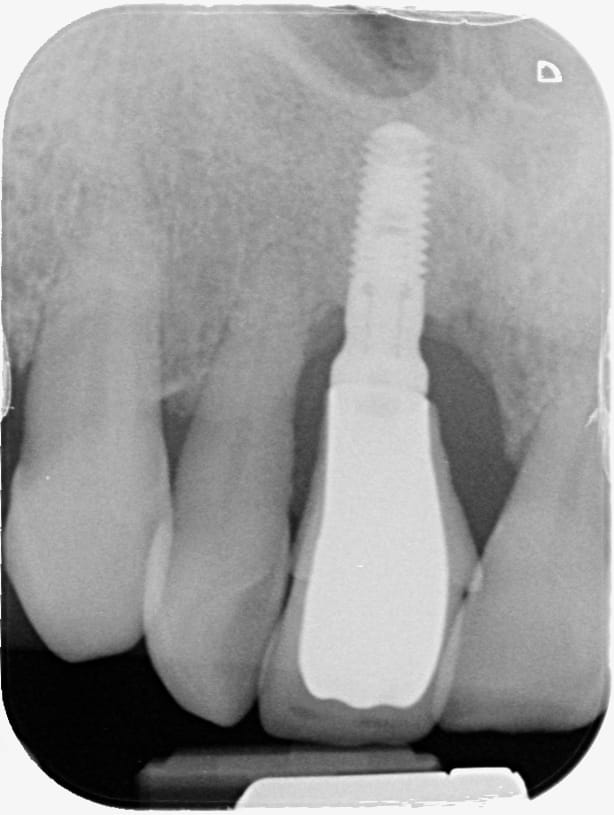

Bonjour implants posés il y a une quinzaine d années.

Si quelqu’un a une idée de la marque merci

sweden martina

https://www.sweden-martina.com/fr_fr/product/implantologie_et_la_chirurgie_-17305/implants_dentaires-17317/premium_one-23219.html